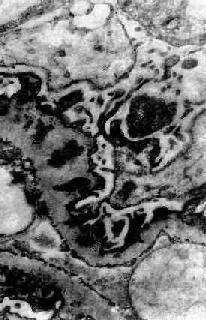

图12-18 膜性肾小球肾炎 电镜下见肾小球毛细血管基底膜表面,上皮细胞下电子致密沉积物,基底膜向表面突出伸入沉积物之间,上皮细胞足突融合